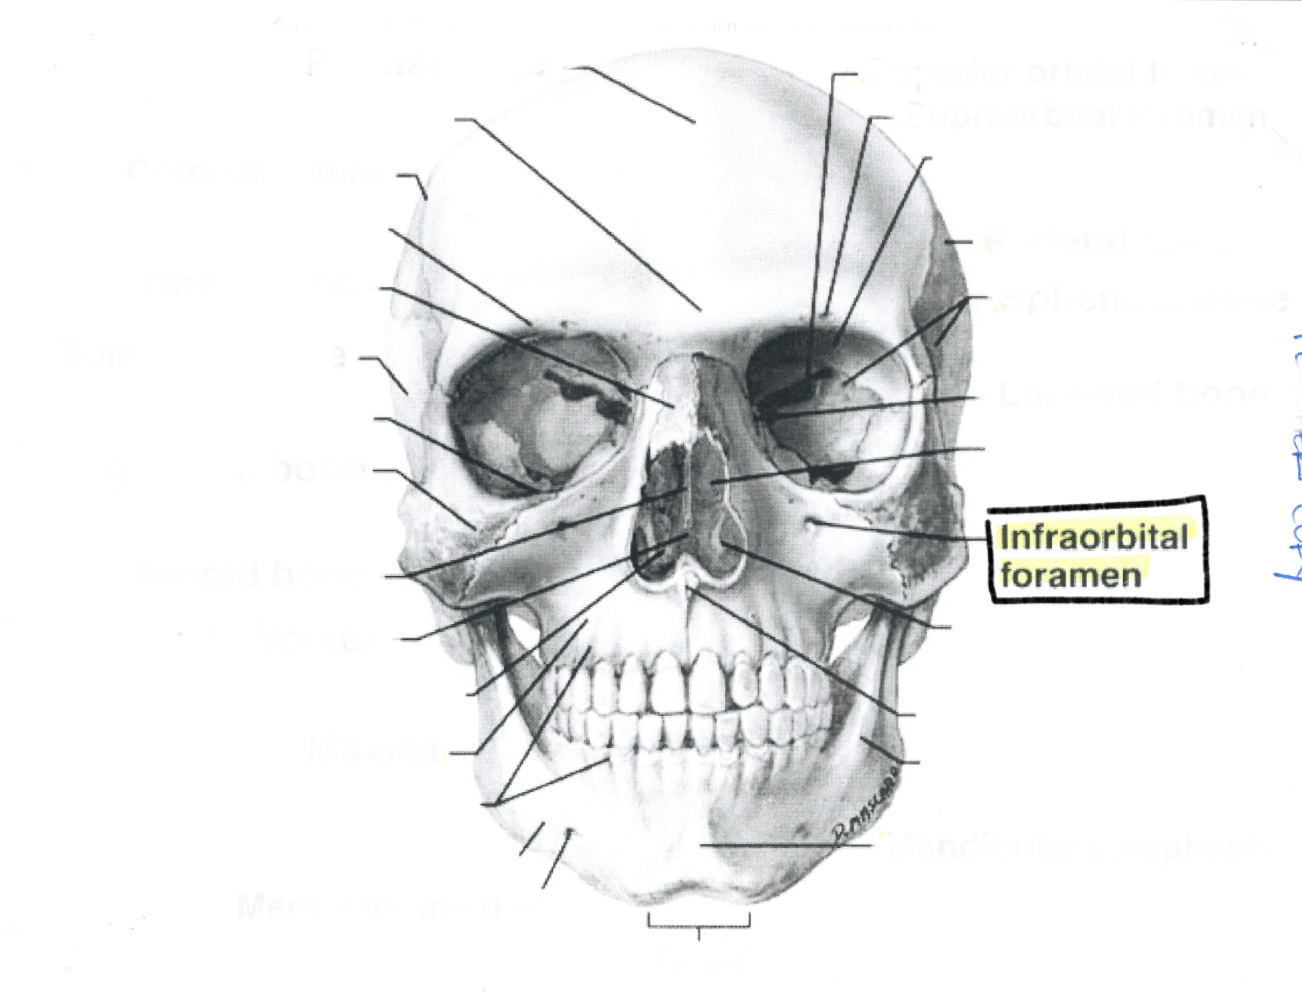

Infraorbital foremen